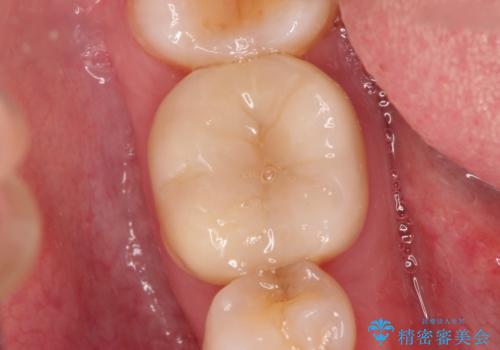

レントゲン上と視診上では確認できなかったのですが、患者様の希望もあり、一度かぶせ物を外して内部を確認し、オールセラミックを再度装着する計画としました。

やはり内部では少量の虫歯がありましたので、拡大鏡使用して虫歯を除去しました。

今回精度の高い治療を行うことで、再治療の可能性を限りになく小さくできました。